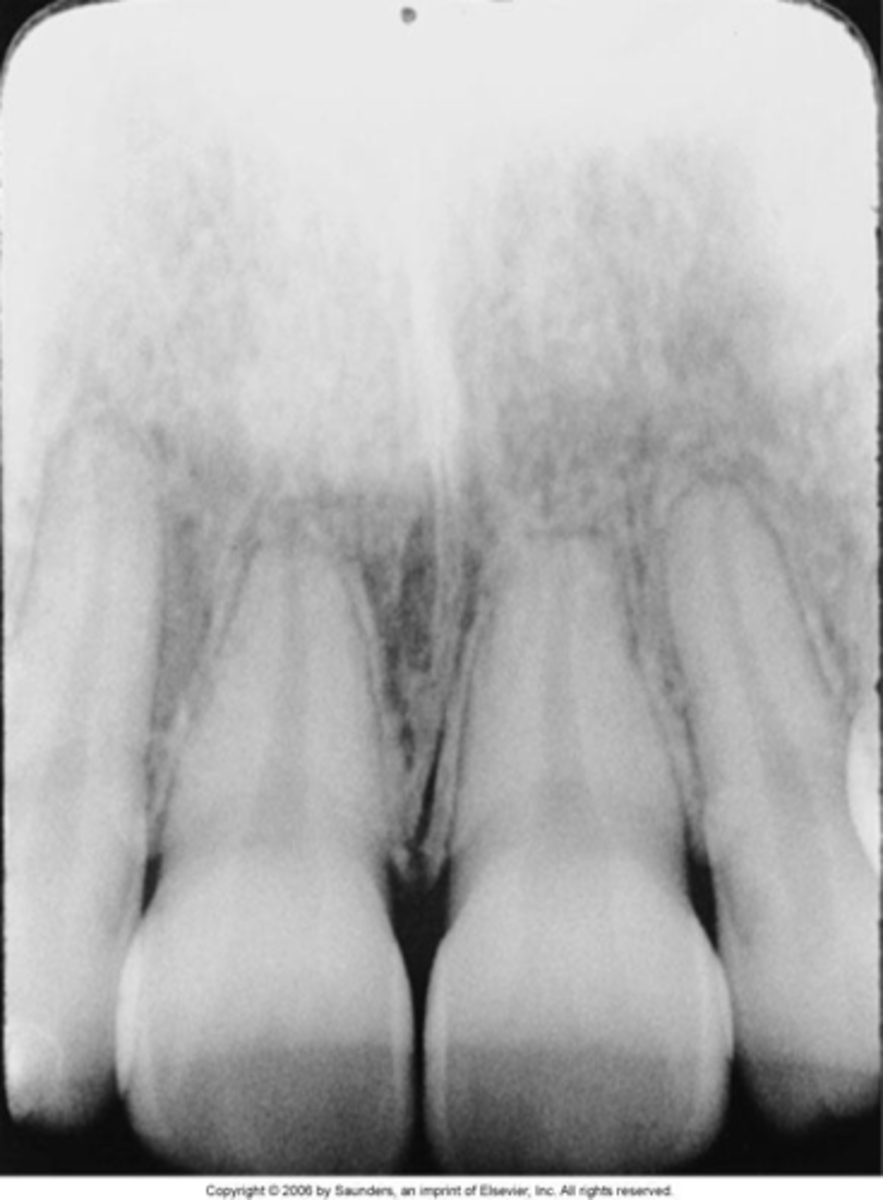

static electricity

thin, black, branching lines

<p>thin, black, branching lines</p>